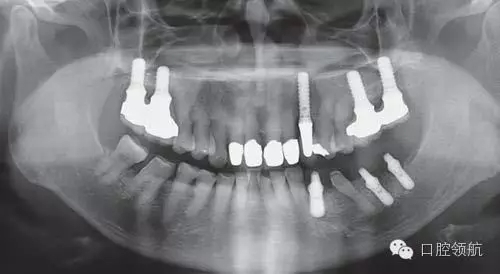

來自于外院的下頜左側(cè)種植病例,術(shù)前X線片診斷嵴頂距下頜神經(jīng)管骨量充分,一次手術(shù)方法植入種植體,第2天頦孔區(qū)有輕微感覺異常,手術(shù)醫(yī)生了解后只是讓隨診觀察,但4個月后癥狀沒有改善,來我院要求進一步檢查。

利用曲面斷層及CBCT檢查埋入部位情況,雖未出現(xiàn)與主訴相關(guān)的神經(jīng)損傷,但無意中卻發(fā)現(xiàn)了種植體的舌側(cè)穿孔(圖1、圖2)。

圖1 術(shù)后的曲面斷層影像。

雖不能確定是裂鉆備洞還是植入種植體所造成的穿孔,但從4個月的病情的發(fā)展看,考慮可能是術(shù)中的舌下動脈損傷導致口底軟組織內(nèi)出血而造成的感覺異常。采用常規(guī)藥物及物理療法開始進行治療。